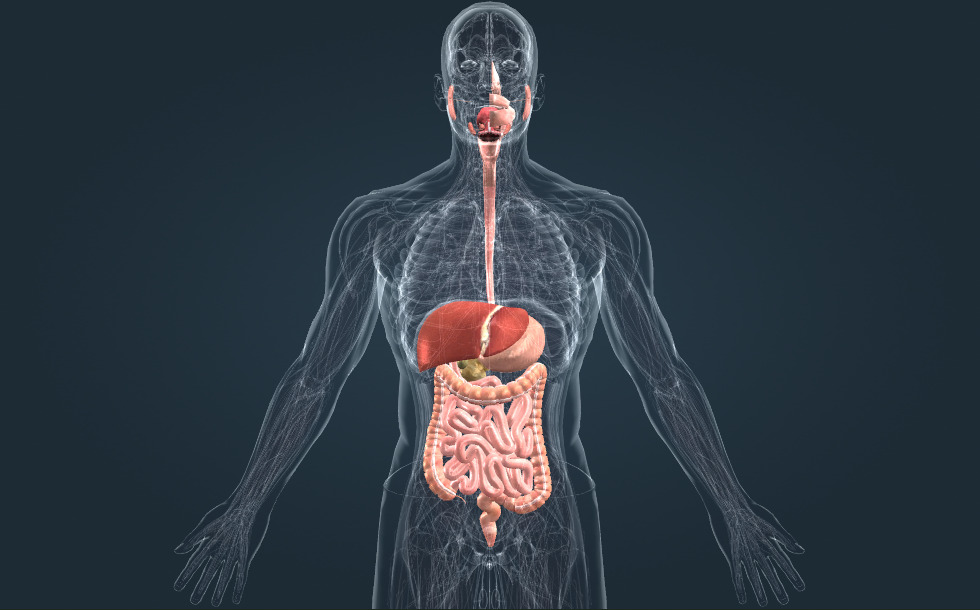

Πεπτικό σύστημα

- στομάχι - Σε αυτό το όργανο γίνεται η πέψη των πρωτεϊνών. Ο γαστρικός χυμός είναι εξαιρετικά όξινος.

- λεπτό έντερο - Σε αυτό το όργανο γίνεται η πέψη των πρωτεϊνών, των υδατανθράκων και των λιπιδίων. Τα θρεπτικά συστατικά, αφού υποστούν την διαδικασία της πέψης, απορροφώνται εδώ.

- παχύ έντερο - Εδώ γίνεται η πέψη του νερού και των μεταλλικών στοιχείων. Η χλωρίδα του βακτηρίου του παράγει τις βιταμίνες Κ και Β.

- ορθό

- συκώτι - Παίζει σημαντικό ρόλο στην αποτοξίνωση και παράγει τη χολή, η οποία βοηθάει στην πέψη των λιπιδίων.

- πάγκρεας - Παράγει τον παγκρεατικό χυμό, ο οποίος βοηθάει στην πέψη των λιπιδίων, των υδατανθράκων και των πρωτεϊνών στο λεπτό έντερο. Επίσης, εκκρίνει την ορμόνη της ινσουλίνης, η οποία δρα για τη μείωση του επιπέδου της γλυκόζης στο αίμα.

- οισοφάγος

- στοματική κοιλότητα

- χοληδόχος κύστη - Ένα κοίλο όργανο σε σχήμα αχλαδιού, όπου η χολή αποθηκεύεται προσωρινά και συμπυκνώνεται.

Το πεπτικό σύστημα είναι υπεύθυνο για την πέψη και την απορρόφηση των θρεπτικών ουσιών.

Τα δόντια τεμαχίζουν την τροφή στο στόμα και εδώ επίσης ξεκινάει η πέψη των υδατανθράκων. Η πέψη των πρωτεϊνών γίνεται στο στομάχι, όπου το περιβάλλον είναι εξαιρετικά όξινο.

Στη συνέχεια, στο λεπτό έντερο απορροφώνται και οι τρεις τύποι θρεπτικών ουσιών, δηλαδή οι πρωτεΐνες, οι υδατάνθρακες και τα λιπίδια. Το παγκρεατικό υγρό, το οποίο εκκρίνεται από το πάγκρεας και περιέχει πεπτικά ένζυμα, αδειάζει εκεί, το ίδιο και η χολή, η οποία εκκρίνεται από το συκώτι και βοηθά στην πέψη των λιπιδίων. Το παχύ έντερο απορροφά το νερό και τα μεταλλικά στοιχεία και η χλωρίδα των βακτηρίων παράγει βιταμίνες.

Το πεπτικό σύστημα είναι υπεύθυνο για την πέψη και την απορρόφηση των θρεπτικών ουσιών. Τα δόντια τεμαχίζουν την τροφή στο στόμα και εδώ επίσης ξεκινάει η πέψη των υδατανθράκων. Η πέψη των πρωτεϊνών γίνεται στο στομάχι, όπου το περιβάλλον είναι εξαιρετικά όξινο. Στη συνέχεια, στο λεπτό έντερο απορροφώνται και οι τρεις τύποι θρεπτικών ουσιών, δηλαδή οι πρωτεΐνες, οι υδατάνθρακες και τα λιπίδια. Το παγκρεατικό υγρό, το οποίο εκκρίνεται από το πάγκρεας και περιέχει πεπτικά ένζυμα, αδειάζει εκεί, το ίδιο και η χολή, η οποία εκκρίνεται από το συκώτι και βοηθά στην πέψη των λιπιδίων. Το παχύ έντερο απορροφά το νερό και τα μεταλλικά στοιχεία και η χλωρίδα των βακτηρίων παράγει βιταμίνες.